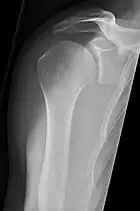

Shoulders

_X-ray_of_a_normal_shoulder.jpg.webp)

These include:

- AP-projection 40° posterior oblique after Grashey

The body has to be rotated about 30 to 45 degrees towards the shoulder to be imaged, and the standing or sitting patient lets the arm hang. This method reveals the joint gap and the vertical alignment towards the socket.[17]

- Transaxillary projection

The arm should be abducted 80 to 100 degrees. This method reveals:[17]

- The horizontal alignment of the humerus head in respect to the socket, and the lateral clavicle in respect to the acromion.

- Lesions of the anterior and posterior socket border or of the tuberculum minus.

- The eventual non-closure of the acromial apophysis.

- The coraco-humeral interval

- Y-projection

The lateral contour of the shoulder should be positioned in front of the film in a way that the longitudinal axis of the scapula continues parallel to the path of the rays. This method reveals:[17]

- The horizontal centralization of the humerus head and socket.

- The osseous margins of the coraco-acromial arch and hence the supraspinatus outlet canal.

- The shape of the acromion

This projection has a low tolerance for errors and accordingly needs proper execution.[17] The Y-projection can be traced back to Wijnblath's 1933 published cavitas-en-face projection.[18]

In the UK, the standard projections of the shoulder are AP and Lateral Scapula or Axillary Projection.[15]